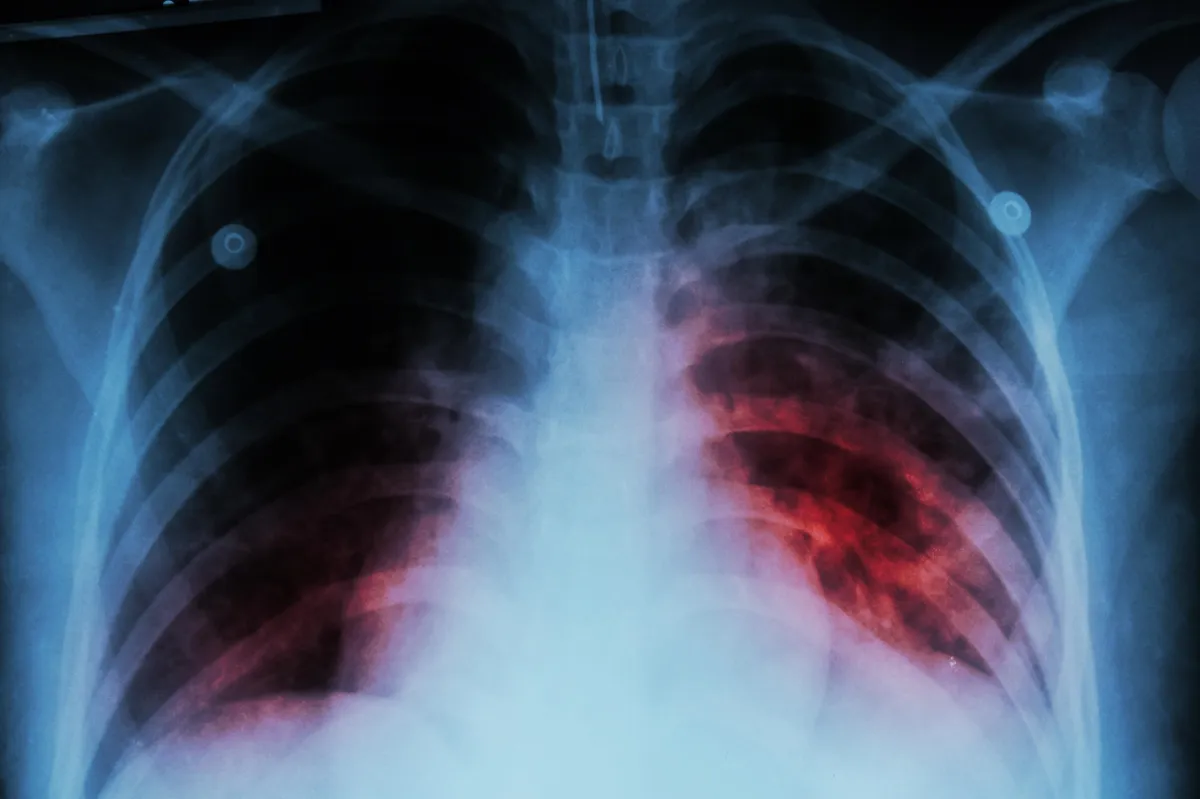

En 2024 se diagnosticaron 967 nuevos casos de tuberculosis en Salta

El Ministerio de Salud Pública trabaja en la búsqueda intensiva de personas sintomáticas y el estudio de contactos para frenar la cadena de contagios.

En el año 2024 se diagnosticaron en la provincia de Salta 967 nuevos casos de tuberculosis, 62 más que los diagnósticos del año 2023. En el año 2022 la cantidad fue de 852.